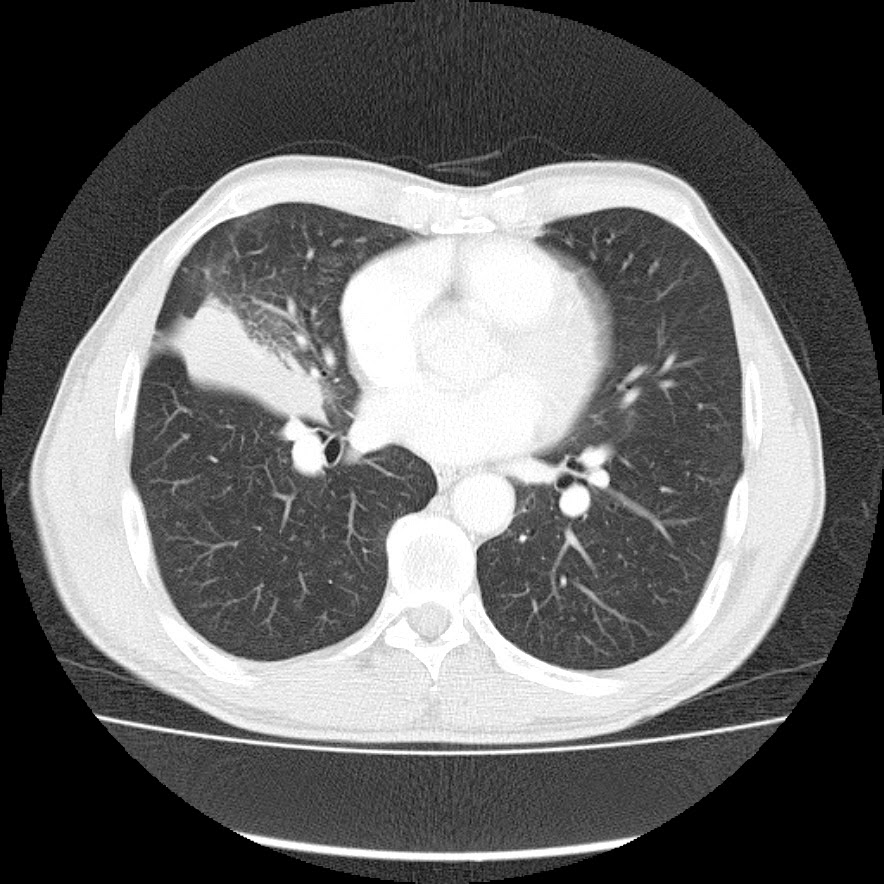

Caso interesante #6

Otro casito de un tórax para localizar la consolidación